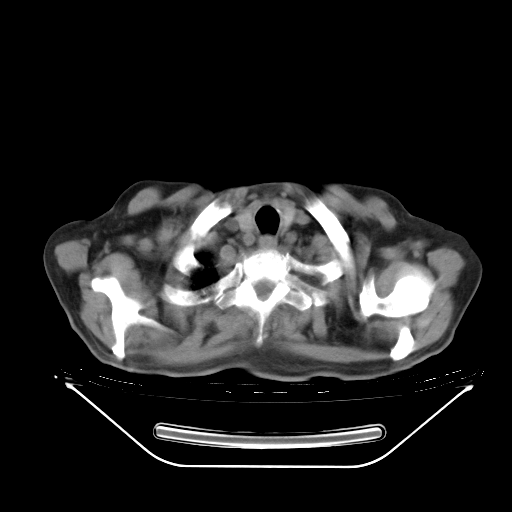

今天复查肺部CT,发现双肺广泛磨玻璃样改变。所以我把3月19日和5月9日相隔50天的肺部CT上传。请大家会诊。

2009年3月19日肺部CT片。

2009年3月19日肺部CT